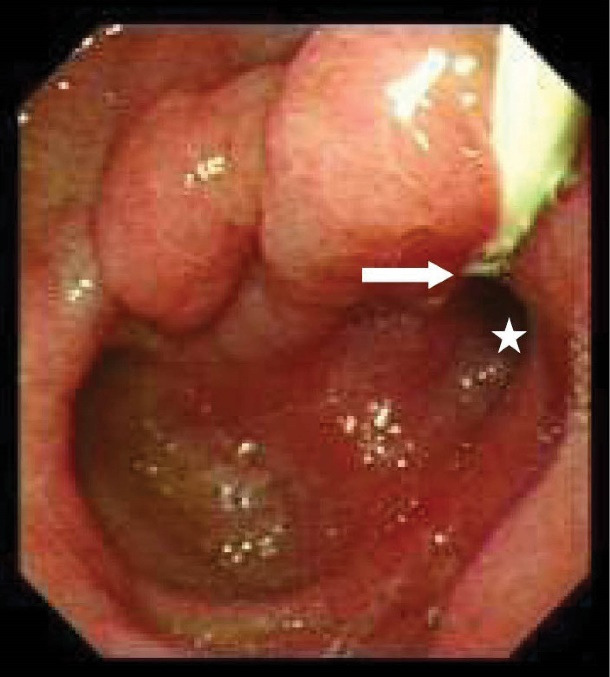

Table 2 shows detailed information about the endoscopic and cholangiographic findings and therapeutic procedure in all patients. Peptic ulcer in different stages, ranging from a scar mark alone to a crater with varying size, was found in the duodenum in 11 (37%) patients. In two patients (6.8%), we observed gastric peptic ulcer (3×2 cm and 2×1 cm in diameter, respectively) located to the incisura angularis and its benign nature was confirmed by biopsy. Ectopic opening opened into the antrum in 2 (6.8%) patients and into the first part of the duodenum in 27 (93%) patients. Both patients with ectopic opening into the first part of the duodenum and into the antrum did not have the classic appearance of the ampulla of Vater and there was a slit-like appearance (Figure 1A), ill-defined mucosal edematous area (Figure 1B) or a circular hole (Figure 1C). In patients with ectopic opening located in the first part of the duodenum, the orifice was located in the posterior wall of the first part of the duodenum. In two patients with ectopic opening located in the antrum, the orifice was located between the incisura angularis and pyloric canal. In 5 out of 29 (17%) patients, the bile duct and pancreatic duct opened to the duodenal bulb separately (Figure 2). All patients had abnormal appearance of the duodenal bulb. Although there was no duodenal ulcer in those patients with ectopic opening to the antrum, both patients had duodenal deformity and apical stenosis. Duodenal deformity associated with apical stenosis was found in 21 out of 29 (72%) patients (Figure 3). None of patients with apical stenosis required balloon dilation. Eight out of 21 (38%) patients with apical stenosis had active duodenal ulcer. Thirteen out of 21 (62%) patients with duodenal deformity and apical stenosis had no visible active ulcer or scar in their duodenum and antrum. Copious amount of bile and/or bile sediment in the stomach was seen in all patients.

This opening anomaly is diagnosed by visualization of the opening site of CBD by endoscopy and cholangiography. The typical appearance of the ampulla of Vater is absent and a slit-like orifice is seen during endoscopic examination. This slit-like opening configuration may reflect a poorly developed or absence of the sphincter of Oddi. In a majority of patients with ectopic opening of CBD into the first part of the duodenum, there is apical stenosis associated with duodenal ulcer.1,11,14–17 There are a few case reports showing that an opening of the CBD into the antrum might cause gastric ulcer.5,10 Excessive bile, bile precipitates1,3 and small gallstones4,5 in the stomach were detected in patients with ectopic opening of the CBD into the first part of the duodenum and into the antrum. The cause of apical stenosis and increased incidence of peptic ulcer in patients with this abnormality is unknown. It has been speculated that bile acids usually precipitate at acidic pH and becomes harmless. However, under alkaline condition where the pH is higher, constant exposure of the duodenal bulb and gastric mucosa to bile acids can induce mucosal inflammation, ulcer and stenosis.3 In our case series, there were copious amounts of bile and/or bile sediment in the stomach and slit-like orifice in all patients. The presence of duodenal deformity together with apical stenosis in 21 out of 29 (72%) patients and active duodenal ulcer in 8 out of 21 (38%) patients with apical stenosis was compatible with previously reported findings in patients with this anomaly. Thirteen out of 21 (62%) patients with duodenal deformity and apical stenosis had no visible active ulcer or scar in their duodenum and antrum. These findings may support the possibility that the presence of apical stenosis in these patients may be related to a congenital abnormality or may be related to fibrosis caused by a completely healed duodenal ulcer.